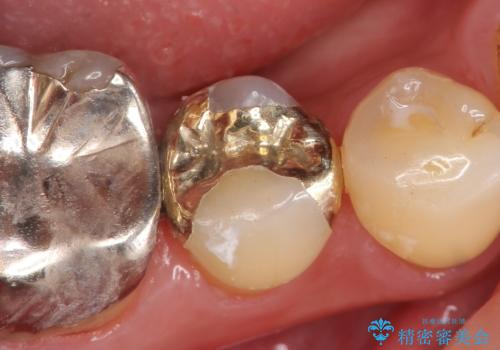

[銀歯を全てセラミックに変えたい] 奥歯のセラミック治療

- 銀歯を全てセラミックに変えたい、左上奥歯の被せ物が取れているところを治療してほしい、長持ちするちゃんとした治療をしてほしいという主訴でご来院されました。

上の左右奥歯第一、第二大臼歯4本と、虫歯になっている下の左右第二大臼歯2本のセラミック治療を行いました。

また、奥歯にセラミックが入り綺麗になると、前歯のプラスチック充填材の茶色い変色が気になられたため、上前歯6本のプラスチック充填を全てやりかえました。

銀歯の部分が全てオールセラミックになると、今まであった違和感も無くなり気持ちよく噛めるようになった、と喜んでくださいました。

銀歯の腐食による体内への重金属蓄積が無くなりますので、メタルフリーになることはやはり身体に優しいのでしょう。